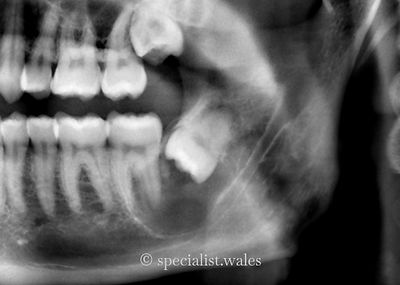

Teeth need removing for many different reasons, but sometimes it can be because there is a cyst related to the tooth. Cysts can also develop in the jaw where a tooth has been previously extracted. Management of a cyst is usually by careful surgical removal. We then send the cyst of to a pathologist for them to provide an exact diagnosis as to the type of cyst that it was. Different cysts have different long-term management as some types of cysts may be prone to recurrence whereas for most they do not recur. Our team of oral surgeons have thousands of hours of operating experience which enables them to approach cysts in careful and efficient manner for their patients. This helps to reduce procedure time and trauma as well as decreasing the risk of complications during or after surgery.